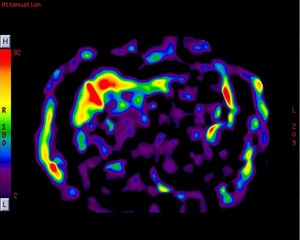

MR-Touch is a Phase Contrast (PC) application that generates an image contrast related to the shear stiffness of soft tissue. MR-Touch is a single touch application that sensitively images the propagation characteristics of acoustic shear waves generated in the tissue of interest. A liver exam is an example of where the application is used.

MR-Touch is performed by synchronizing the Gradient Echo (1.5T pulse sequence used) used with acoustic waves that are applied with an external MR-Touch Device. The pulse sequence is modified with an oscillating Motion Encoding Gradient (MEG). The external acoustic driver is triggered by the PSD so that the MEG is synchronized with the external acoustic wave. The duration of the MEG is the same as the period of the mechanical vibration. A phase shift occurs in the MR signal, which correlates with the mechanical excursion. An algorithm is used to derive a relative stiffness map and wave images from the phase images.

MR-Touch acquisition generates the following image types: magnitude, phase maps, wave maps. Six relative stiffness images are reconstructed for each slice location. The relative stiffness images are reconstructed in color and grey scale, and in masked and un-masked versions. Mask portion is depicted as a checkerboard pattern on the image. It is created to identify regions that should not be included in ROI measurements.